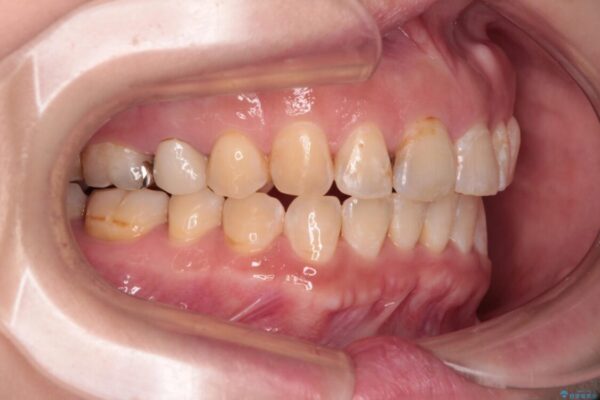

飛び出た上の前歯を気にして来院された患者様です。

奥歯の咬み合わせは、上顎歯列が理想的な一よりも数mm前方にある状態でした。

なるべく早めに治療を終えたいとのことで、補助装置を用いて上顎臼歯を後方に移動させ、同時にワイヤー装置にて整えることとしました。

舌の突出癖が原因で上下の歯に大きなスペースが生じていたため、舌のトレーニングをしっかり行っていただくことで、上顎歯列をスムーズに移動させることができました。

治療途中

• 【モニター】飛び出た前歯を整えたい ワイヤー矯正治療 治療途中画像